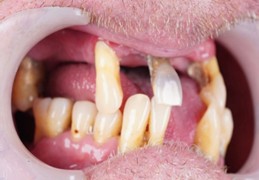

Jason had been living with poorly fitted removable dentures that caused discomfort and were not functional, leaving him frustrated with his oral health. Additionally, the dentures were exacerbated by chronic periodontitis, leading to further oral complications. His primary concern was the inability to eat, speak, and smile confidently due to the poor fit and deteriorating condition of his dental prosthesis.

Dr. Namratha diagnosed Jason with missing teeth, decayed and ill-fitting dentures, compounded by chronic periodontitis. These issues resulted in the need for a comprehensive full-mouth rehabilitation plan, including advanced implantology techniques to restore both function and aesthetics.